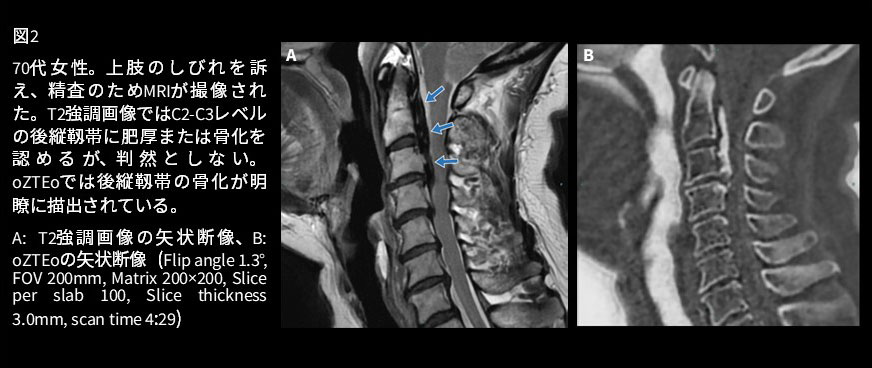

MRIで皮質骨を評価する手法は他にも様々あります。短いTEで撮像するUTE法(Ultra short TE)、Gradient echo法で撮像するT1強調画像やT2*強調画像の反転画像が代表として挙げられます。これらの撮像法では靱帯や腱などの構造も骨皮質と同程度の信号で描出されてしまい、骨皮質だけを白く 描出することができません。

oZTEo、3D-T1強調画像を反転させたBone like image、UTE で撮像したBone like image、multi-echoで収集したT2*強調画像を反転させたBone like imageの画像を供覧します(図1)。Bone like imageの方が比較的短い時間で高分解能に撮像でき 、骨梁構造がより明瞭です。oZTEoはよりCTに近いコントラストで皮質骨を描出することができ、靱帯や腱の描出でBone like imageとの差異がよくわかります。骨のみを強調して描出できる点で、oZTEoこそ真にBone imageと言えると感じています。